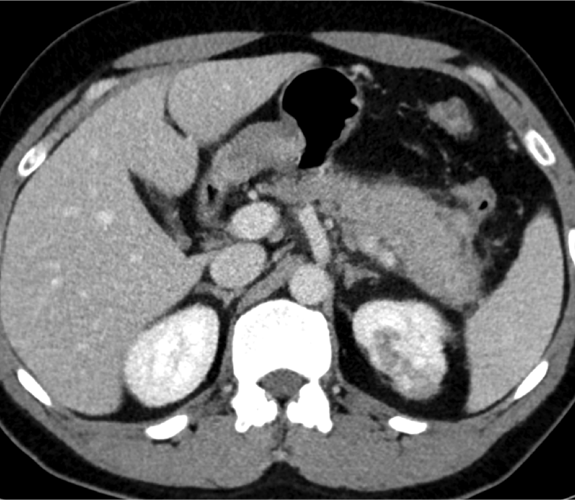

Hombre de 39 años con antecedente de fibrosis retroperitoneal.

Se solicita TC porque en RM externa realizada para control de la fibrosis retroperitoneal se informa de sospecha de neoplasia de cola de páncreas.

3. ¿Cuál es tu diagnóstico?

- A. Tumor pseudopapilar sólido pancreático con metástasis renales izquierdas.

- B. Linfoma pancreático -forma localizada- y lesiones atróficas renales izquierdas secundarias a fibrosis retroperitoneal.

- C. Lesión metastásica en páncreas de tumor primario renal.

- D. Pancreatitis autoinmune en contexto de enfermedad relacionada con la IgG4.

- E. Sarcoidosis con afectación pancreática y renal.